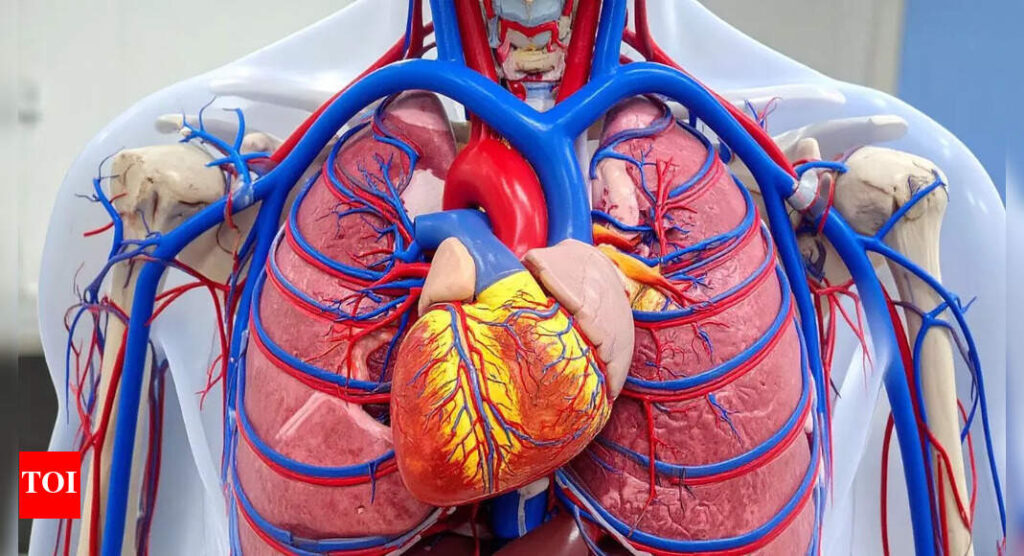

Arteries are the primary blood vessels responsible for transporting oxygen-rich blood from the heart to every organ and tissue in the body. This circulation is essential because oxygen fuels cellular activity, ensuring that the brain, muscles, and organs function properly.Healthy arteries are flexible, elastic, and free of obstruction, allowing blood to flow smoothly. However, over time, substances such as cholesterol, fatty deposits, calcium, and other cellular waste products can accumulate along the artery walls. This buildup leads to atherosclerosis, a condition that gradually narrows and stiffens the arteries.When arteries are constricted, the heart has to work harder to pump blood, and the restricted flow can deprive vital organs of oxygen. In the case of coronary arteries, this reduced flow often results in coronary artery disease (CAD), a condition that can trigger chest pain, heart attacks, or even sudden cardiac death.

How healthy arteries protect your heart

The health of arteries directly determines the health of the heart. Narrowed or stiff arteries force the cardiovascular system into overdrive, increasing the risk of hypertension, stroke, kidney disease, and peripheral artery disease. Conversely, flexible and resilient arteries support better circulation, stable blood pressure, and efficient heart function.Maintaining artery health is therefore not only about avoiding life-threatening conditions but also about preserving overall vitality, energy, and quality of life as one ages.Board-certified Interventional Cardiologist Dr. Sanjay Bhojraj has decades of experience treating patients with cardiovascular conditions. Through his clinical practice and public awareness initiatives, he emphasizes that artery protection is not about drastic interventions but about consistent lifestyle choices.In one of his health-focused posts, he reminded his audience: “Your arteries don’t care about quick fixes. They care about what you do every single day. After two decades as a functional cardiologist, here are the four things I’ve seen make the biggest difference in keeping arteries flexible, resilient, and healthy—no prescriptions required.”